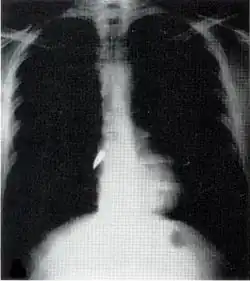

Assessment and treatment

Assessment can be difficult because much of the damage is often internal and not visible.[4] The patient is thoroughly examined.[2] X-ray and CT scanning may be used to identify the type and location of potentially lethal injuries.[2] Sometimes before an X-ray is performed on a person with penetrating trauma from a projectile, a paper clip is taped over entry and exit wounds to show their location on the film.[2] The patient is given intravenous fluids to replace lost blood.[2] Surgery may be required; impaled objects are secured into place so that they do not move and cause further injury, and they are removed in an operating room.[2] If the location of the injury is not obvious, a surgical operation called an exploratory laparotomy may be required to look for internal damage to the organs in the abdomen.[17] Foreign bodies such as bullets may be removed, but they may also be left in place if the surgery necessary to get them out would cause more damage than would leaving them.[12] Wounds are debrided to remove tissue that cannot survive and other material that presents risk for infection.[2]